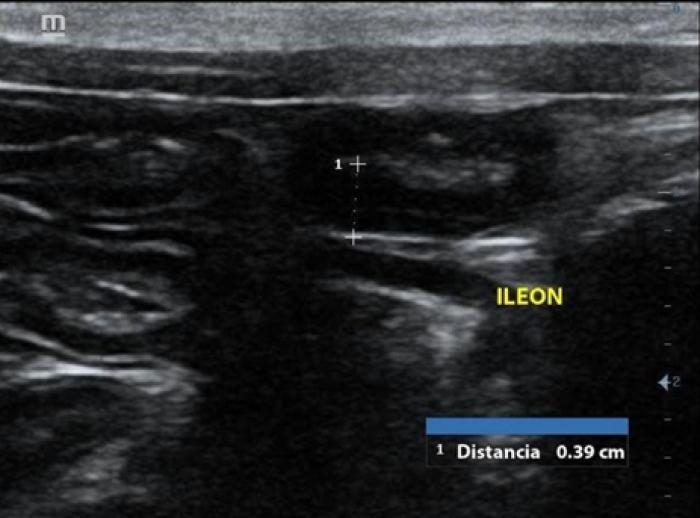

en urianálisis presentó una DU de 1.038, presencia de sangre secundario a la toma de muestras y proteinuria relacionada. Presión arterial promedio de 152/92, considerado como pre hipertensión, perfil tiroideo sin alteraciones y en ultrasonido abdominal se observa engrosamiento del segmento intestinal del duodeno (0.30 cm), yeyuno en mediciones normales y engrosamiento del íleon (0.39 cm) con pérdida de la estratificación normal, presencia de linfonodos iliacos reactivos y presencia de sedimento en el lumen de la vesícula biliar (Figuras 2 y 3). El coproparasitoscópico directo fue negativo y la tinción kinyoun fue positiva aCryptosporidium.

Los signos clínicos, así como los hallazgos que suelen observarse en el ultrasonido abdominal tales como aumento en el grosor de las capas intestinales, pérdida de definición de las capas, linfadenopatía reactiva y peritoneo hiperecoico son comunes para ambas enfermedades, por lo que en ningún caso se debe emitir un diagnóstico por este método ni basado en signología clínica. El promedio de las mediciones de la pared intestinal de ambos gatos superaron los 0.28 cm, por lo cual se justificaron la toma de las biopsias. La prueba gold standard para la diferenciación de las enteropatías crónicas felinas es el examen histopatológico de muestras de biopsias teñidas con H&E5.